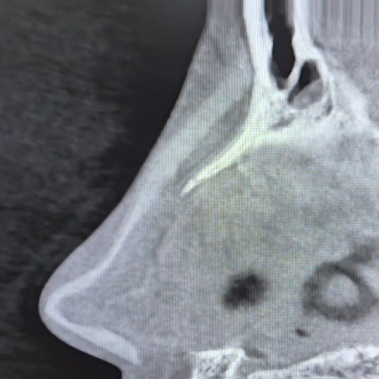

2 ตรวจดูทรงซิลิโคน จมูกไม่สวยซักที CTบอกได้ เพราะ การตรวจด้วยเครื่องเอกซเรย์คอมพิวเตอร์ความละเอียดสูง สามารถบอกได้ว่าปัญหาความไม่สวยเกิดจากอะไร ทรงSILICONEจมูก ยาวหรือสั้นเกินไป SILICONEตรงหรือโก่ง หัวใหญ่หัวเล็ก การตรวจด้วยเครื่องเอกซเรย์คอมพิวเตอร์ความละเอียดสูง บอกได้ทั้งหมด จะเห็นว่ารูปทรงของSILICONE เมื่อเสริมเข้ามาจริงๆแล้ว ยังต้องมีการปรับตัวให้เข้ากับเนื้อเยื่อรอบด้านทำให้ไม่สามารถประเมินจากภายนอกเพียงอย่างเดียวได้

3 ความเสี่ยงของการทะลุ ในกรณี มีการดันของซิลิโคนมากเกินไปจนผิวหนังบางขึ้น การตรวจด้วยเครื่องเอกซเรย์คอมพิวเตอร์ความละเอียดสูง สามารถบอกได้ โดยเฉพาะอย่างยิ่งการทะลุจากด้านในรูจมูก พราะส่วนใหญ่ของการทะลุไม่ได้เกิดบริเวณผิวด้านนอก แต่เกิดด้านในรูจมูก ซึ่งยากต่อการตรวจสอบ